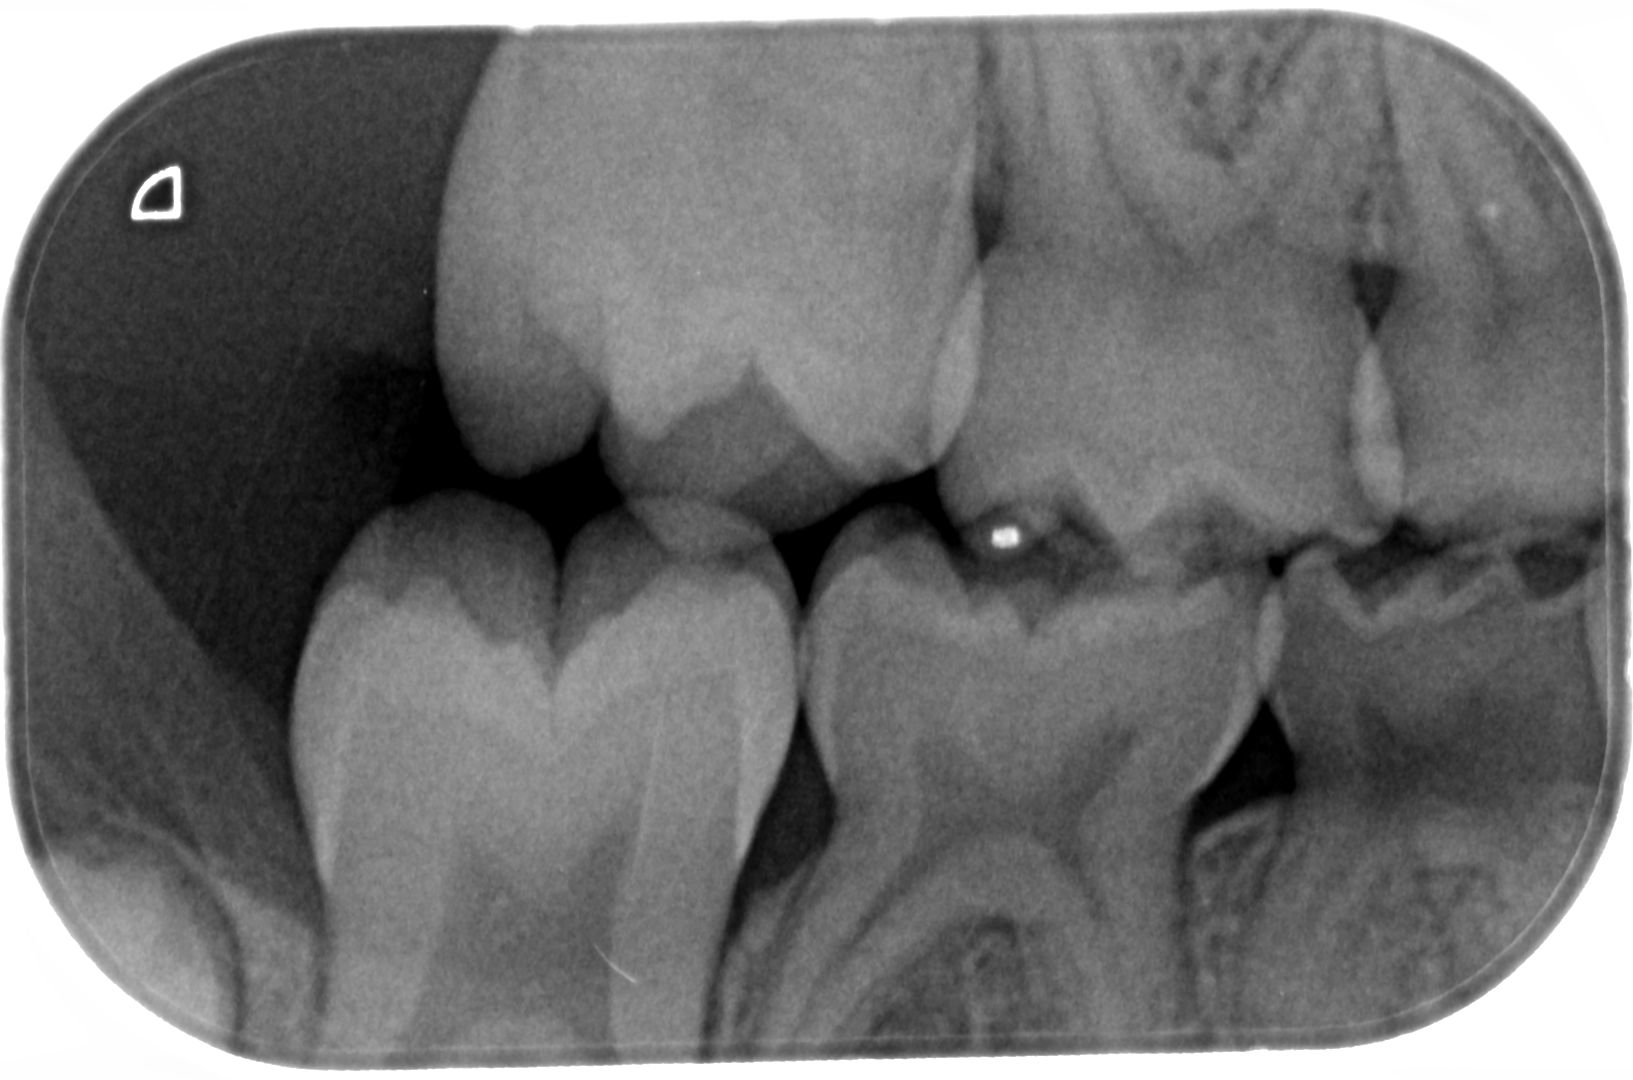

Beste tandarts, Bijgevoegd 2 XR-beelden van de melktand kiezen van onze dochter van 6. Bij een controle bij onze tandarts werden haar tanden visueel gaaf bevonden, maar wou men toch graag een foto maken. Hierop ziet de tandarts 6 gaatjes die ze in 3 sessies wil open maken en vullen. Uiteraard willen wij dat de gaatjes behandeld worden indien nodig. Echter doordat we het gevoel hebben dat er bij elk van ons steeds meerdere problemen gevonden worden waar we geen hinder van ondervinden, zou ik graag een tweede opinie vragen. Omdat ik zelf de beelden niet kan interpreteren, mijn vraag dus of er effectief 6 gaatjes te zien zijn en of het vullen hiervan aanbevolen is. Alvast bedankt voor uw hulp!

Ik zie mogelijk een gaatje in de 55 en 54. Mogelijk omdat er een overprojectie is. Maar dusdanig klein dat ik zou afwachten tot uw dochter wat ouder is. Na een jaar een vergelijking foto. Maar ik zie geen zes op deze foto's.